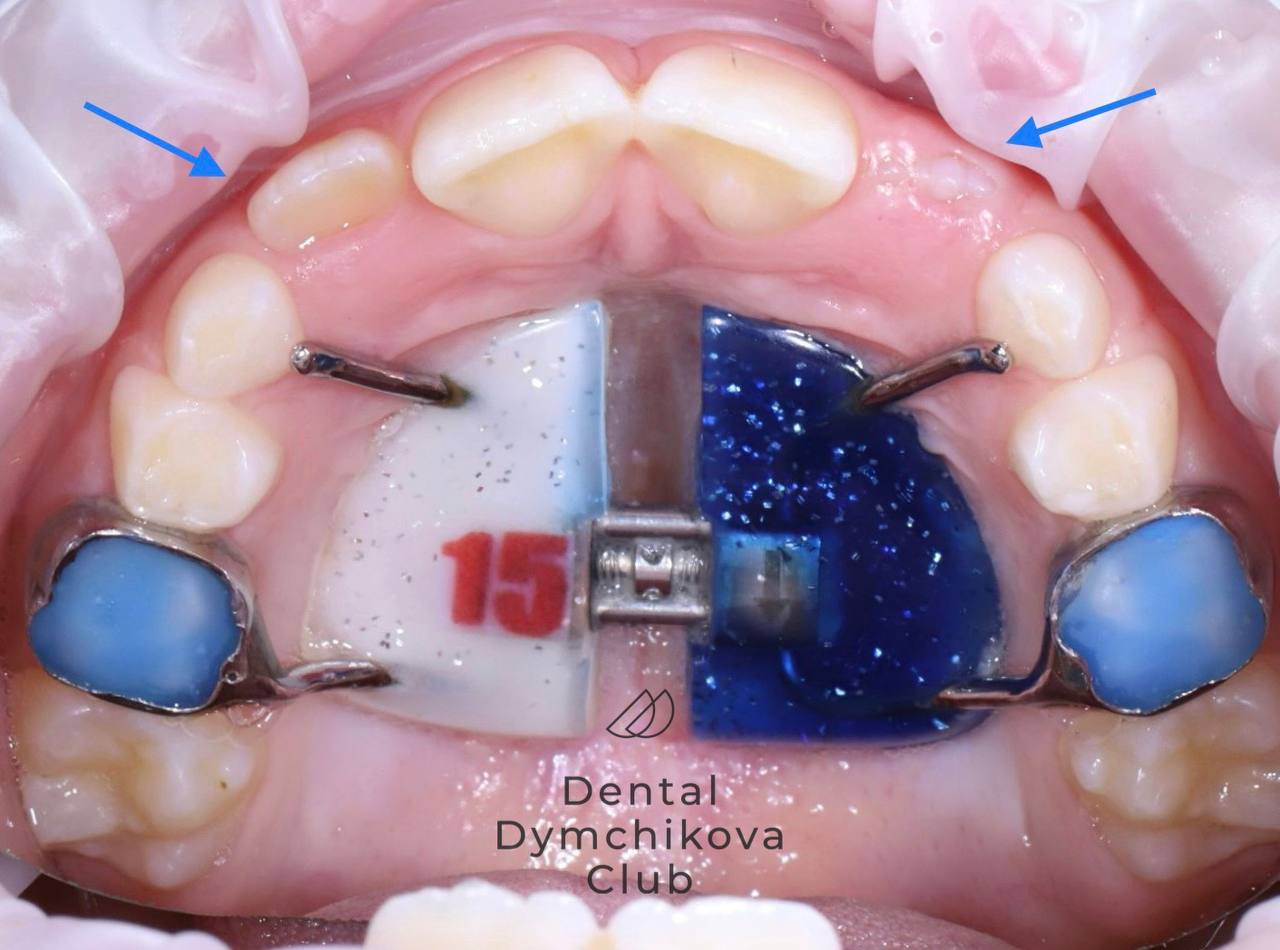

Аппарат Хаас (часть 1)

Пациент, 7 лет.

Жалобы: у мамы переживания по поводу того, что не прорезаются верхние резцы у ребенка.

Объективно: сужение верхней челюсти, недостаток места для прорезывания постоянных боковых резцов и клыков. Нарушена функция языка: язык находится на нижних зубах и при глотании упирается в верхние резцы, что провоцирует открытие прикуса и не дает верхней челюсти развиваться в полном объеме.

Желание ребенка: чтобы на пластинке было число 15, потому что в футбольной команде у него номер 15.

Лечение: после консультации и диагностики был фиксирован несъемный аппарат для расширения верхней челюсти (аппарат Хаас). Было произведено быстрое небное расширение в течение месяца, также назначены занятия с миотерапевтом для нормализации положения языка.

Итоги лечения: получено место для прорезывания зубов, резцы находятся в стадии прорезывания. Ширина верхней челюсти достаточна. Сейчас пациент находится под контролем врача-ортодонта, продолжает занятия с миотерапевтом. После прорезывания боковых резцов планируется фиксация брекет-системы 2 на 4 (брекеты на постоянные резцы и первые жевательные зубы).

Срок лечения (на данный момент): 5 месяцев (5 посещений у ортодонта)

Доктор: Ефимова Дарья Юрьевна